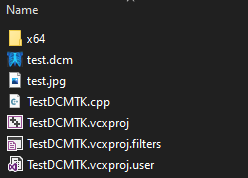

If everything went well, you should have created the test.dcm file in the project folder containing the .cpp file and where the test image was placed.

The data in this file can be displayed with the DCMTK console utilities, by programming C++ code using the libraries, or by using a DICOM Viewer.